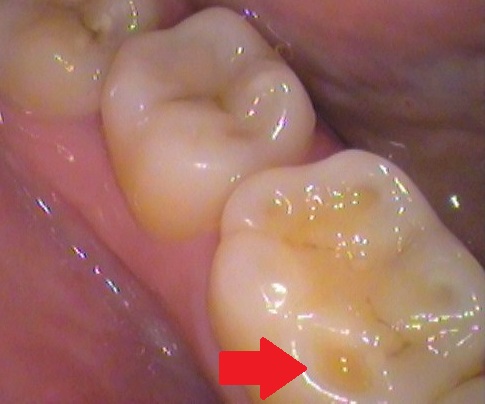

【奥歯の小さい穴】

矢印の箇所ですが、歯と歯の間に小さい隙間が見られます。

一見、小さい穴ですが、中を削っていくと☟